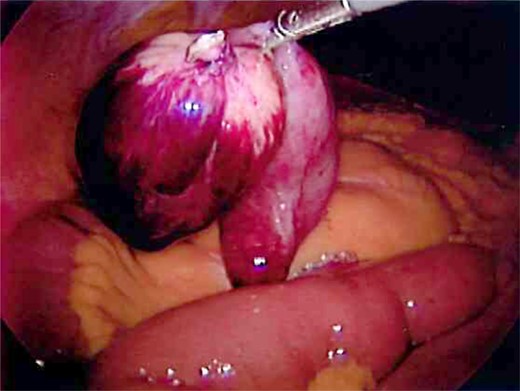

Laparoscopy was performed and a large Meckel's diverticulum was identified ∼30 cm proximal from the ileocecal valve. It had twisted 360° and was swollen and gangrenous at the distal half (Fig. 1). The tip of the diverticulum contained a 3-cm long mesodiverticular band that was attached to the mesentery of an adjacent loop of terminal ileum (Fig. 2). The mesodiverticular band was surgically divided, and the diverticulum was then de-torsed revealing a normal appearing base (Fig. 3). The diverticulum was excised along its base using an endoscopic stapler (Fig. 4). The surgery was completed with an appendectomy. On postoperative day one, the patient was doing well and was discharged home.

Mesodiverticular band connecting the tip of the Meckel's diverticulum to adjacent small bowel mesentery.